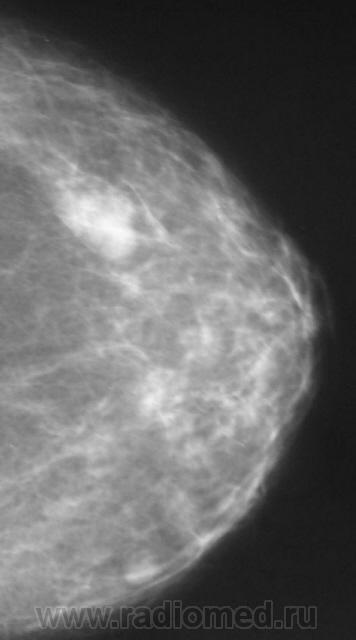

Ещё одна интересная маммография

Жалоб пациентка не предъявляет, просто иногда ощущает дискомфорт в мол.железах.

Кистозный ФАМ с одной стороны просто ФАМ с другой (где право-лево не указано на снимках)

Где прямые, где косые? Вероятно кисты, но могут быть и фиброаденомы, надо УЗИ и при кистах - пункционное удаление содержимого, при фиброаденомах - секторальная резекция.

А, мне, что-то больше симпатично, как "фиброаденомы".

Гадать кисты это или фиброаденомы без УЗИ - дело не благодарное, почему кисты ставлю на первое место потому, что чаще кисты бывают множественными.